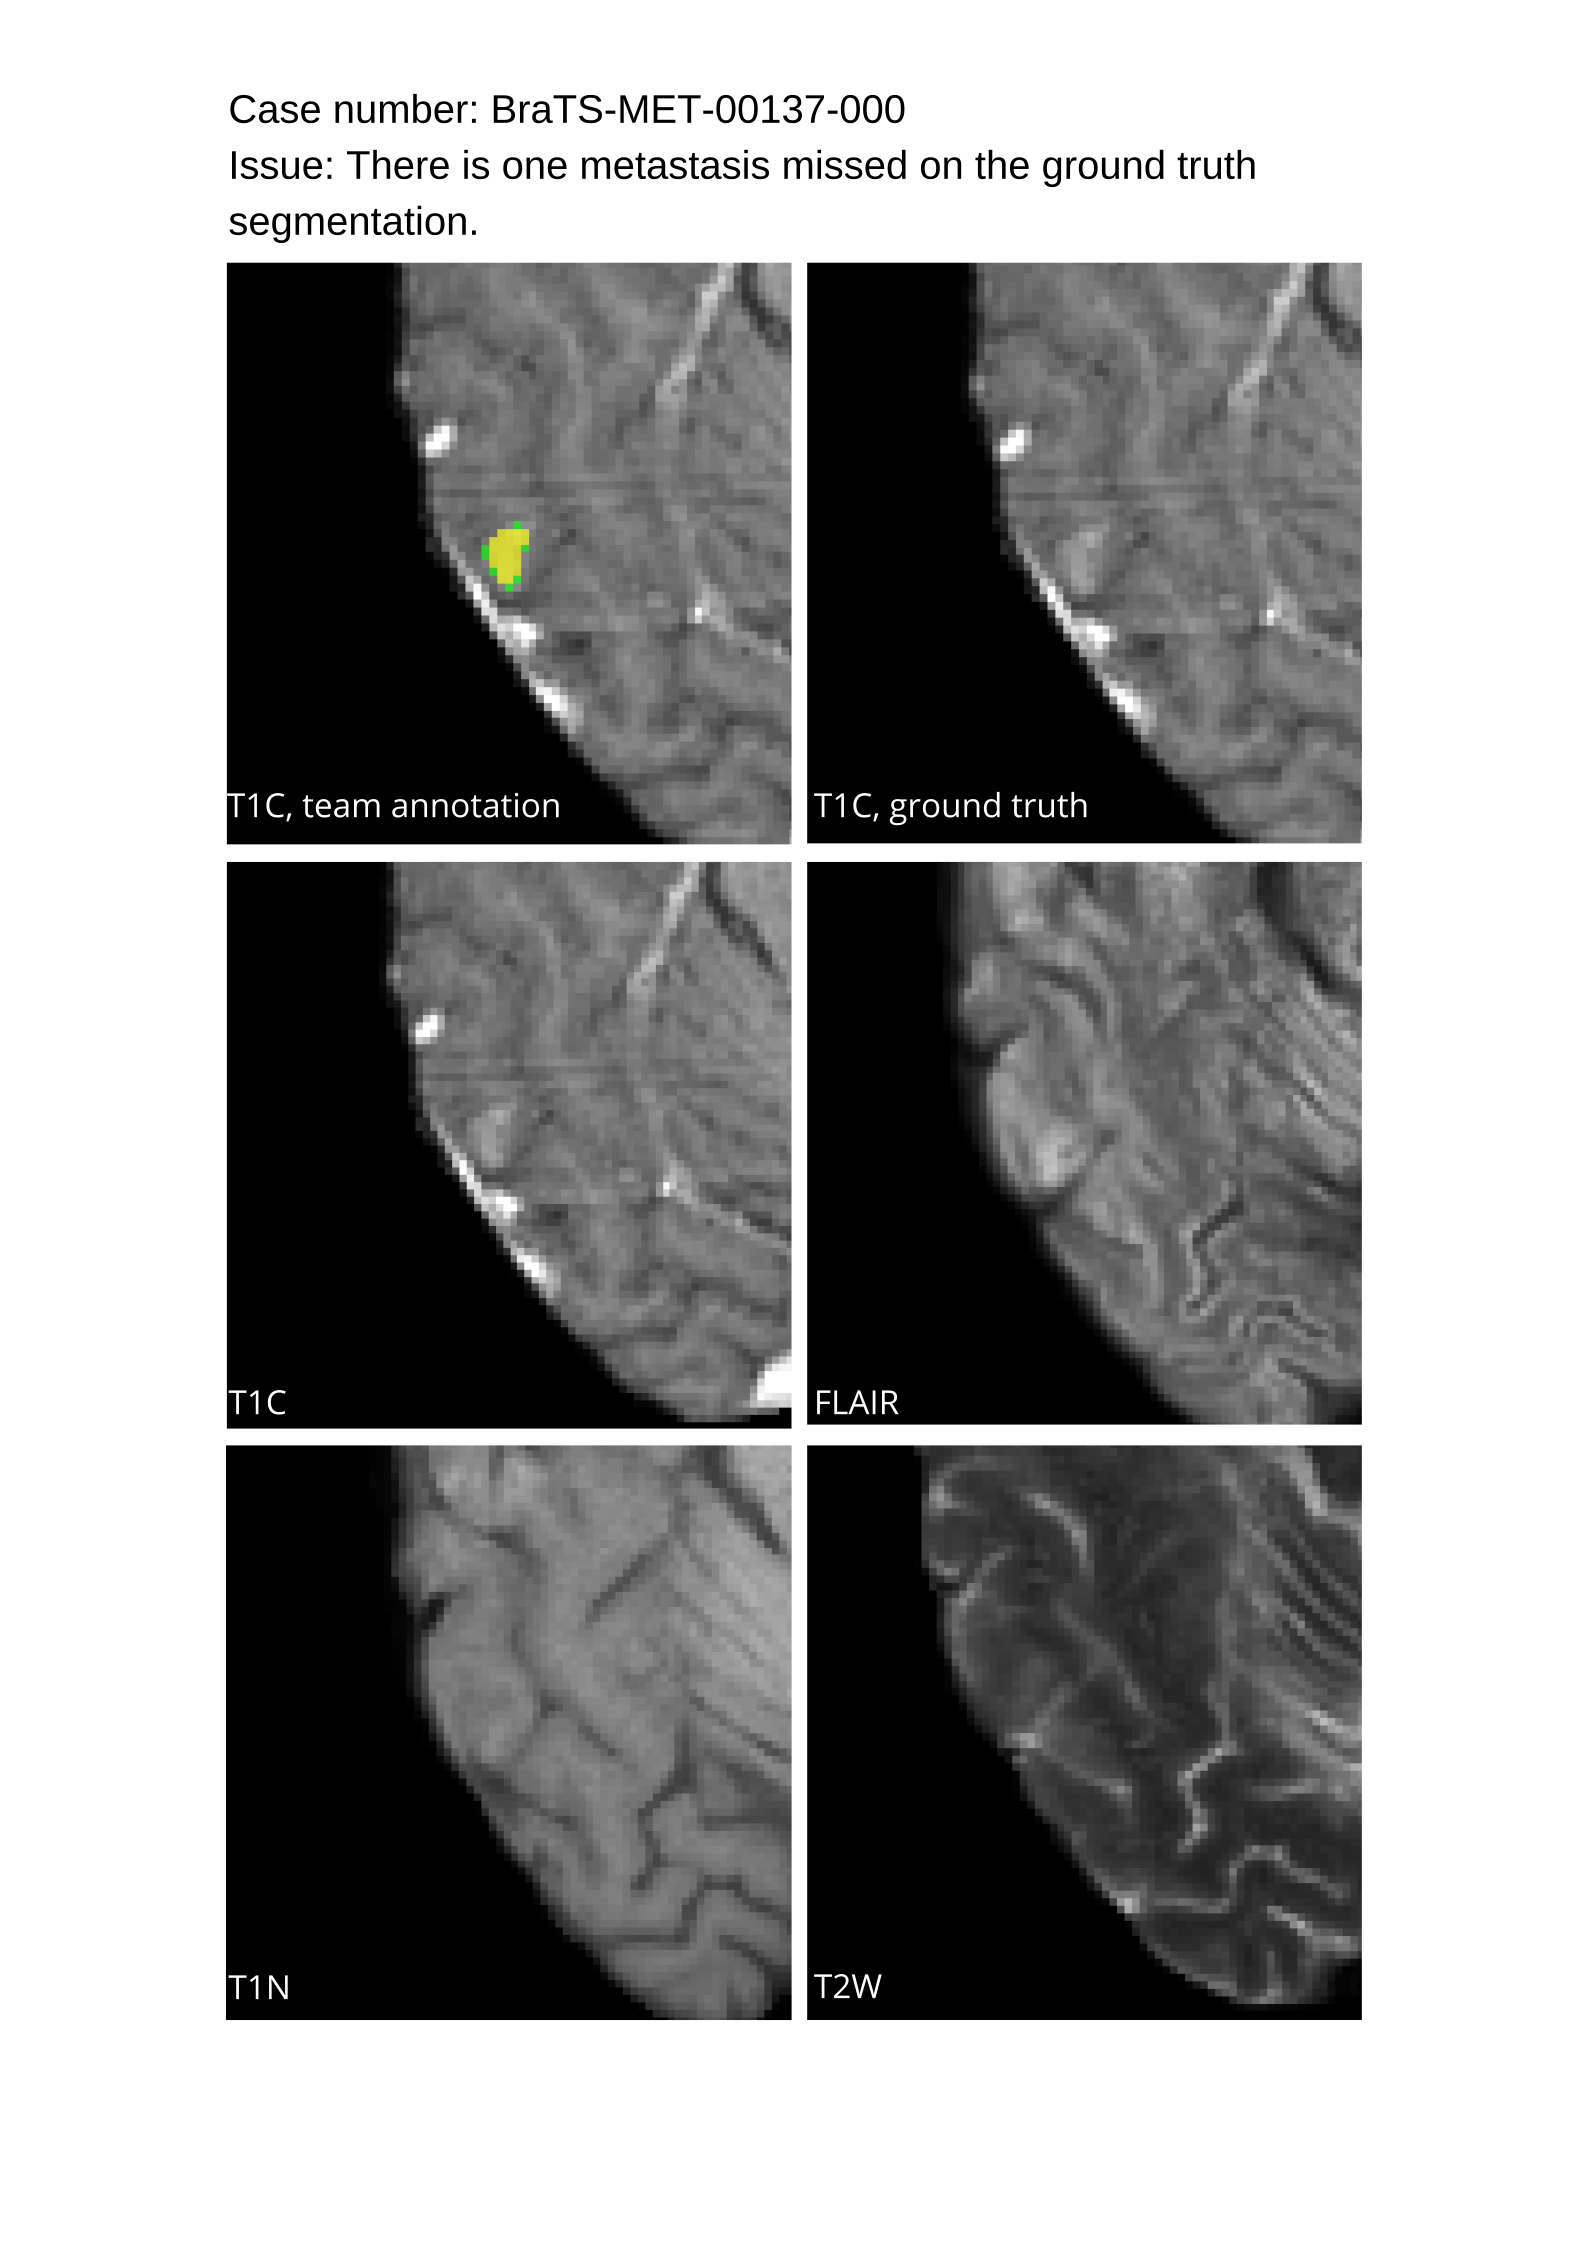

4.9 Common Errors of Automated Segmentations

Based on observations from previous BraTS challenges, common errors in automated segmentations were identified. The most typical errors in the current challenge included:

1. 1.

Automated algorithms missing small metastases. Enhancing metastasis was fused using the minority voting algorithm to aggregate all enhancing tumor voxels identified by the three algorithms. However, many small metastases were missed and were manually segmented by neuroradiology attendings.

2. 2.

Segmentation of white matter changes from microvascular disease. Peritumoral edema segmentations were checked by neuroradiology attendings and modified.

3. 3.

The segmentation of non-enhancing lesions that have intrinsic T1 hyperintensity. Voxels with intrinsic T1 hyperintensity were manually removed from ET segmentations.

These insights led to specific adjustments in the annotation process to enhance accuracy.